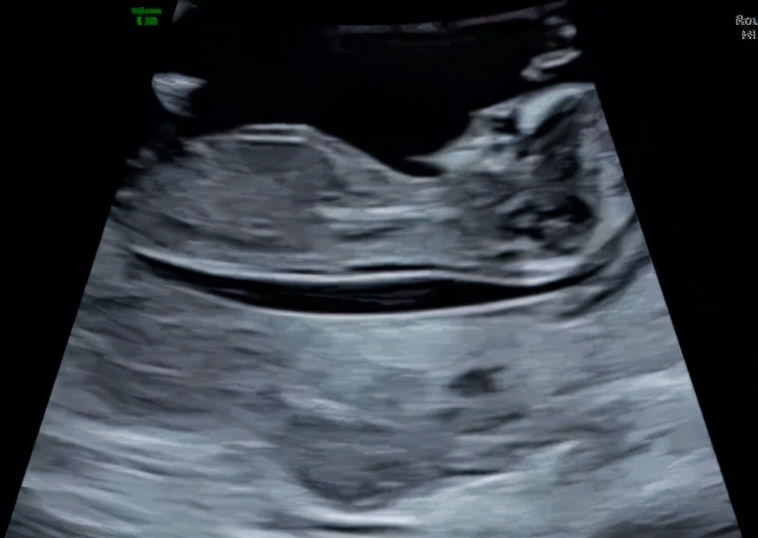

第三次 16-19周

为唐筛检查提供超声数据,估计风险率。检查双顶径,头围,腹围,股骨长度, 羊水深度,胎位,胎盘位置的描述。不需要憋尿。